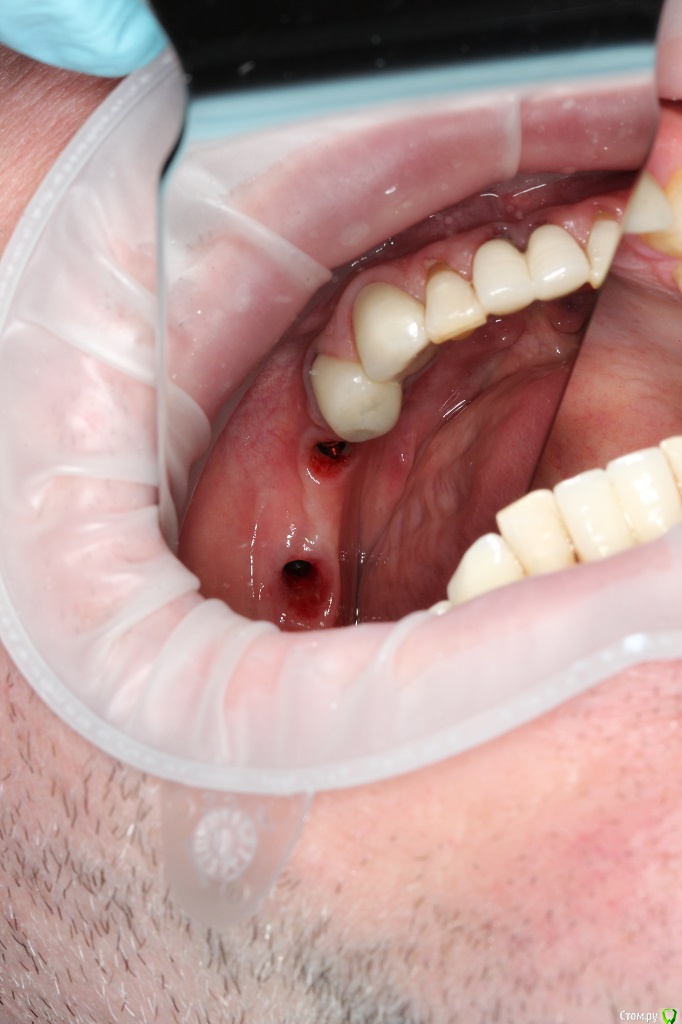

Dr.Sham Опубликовано 11 марта, 2015 Поделиться Опубликовано 11 марта, 2015 (изменено) Год назад в другой клиник пациенту устанавливали имплантаты, вроде одномоментно с удалением.На сегодняшний день жалобы стандартные для такой ситуации (пища застревает, запах изо рта).Коронки демонтировал, увидел "козырьки", нехватку десны, отсутсвие 3 мм от профиля прорезывния до платформы.По КТ, стандартно для селекта - отсутсвие 1,5-2 мм кости по кругу, в полости рта признаков воспаления я не диагностирую, отделяемого нет. На данный момент просто выполировал шейки, чтобы не было козырьков, но пища застревает еще больше, насколько я понимаю. В области 36 - язычно норм, вестибулярно - всего 1 мм, расщепить лоскут вестибулярно и подсадить трансплантат с неба, получим ширину, но не высоту, но как без козырька размоделировать коронку?В области 45 - вестибулярно высота есть, а язычно всего 1 мм, расеплять язычно ищечно и добавлять десну?Если так, то на фдмках вести или как?В области 46 - высота есть по кругу, но нет ЗКПД, какой метод предпочесть, чтобы сохранить уже имеющуюся БШ?Как выходить из ситуации?Кто что думает. Спасибо.Теоретически можно вынуть болты, но интегрированный нобель пару раз выкручивал - выпиливал, удовольствие сомнительное.ПС кстати обратите внимание на цемент на границе коронка-абатмент! Изменено 11 марта, 2015 пользователем Dr.Sham Ссылка на комментарий